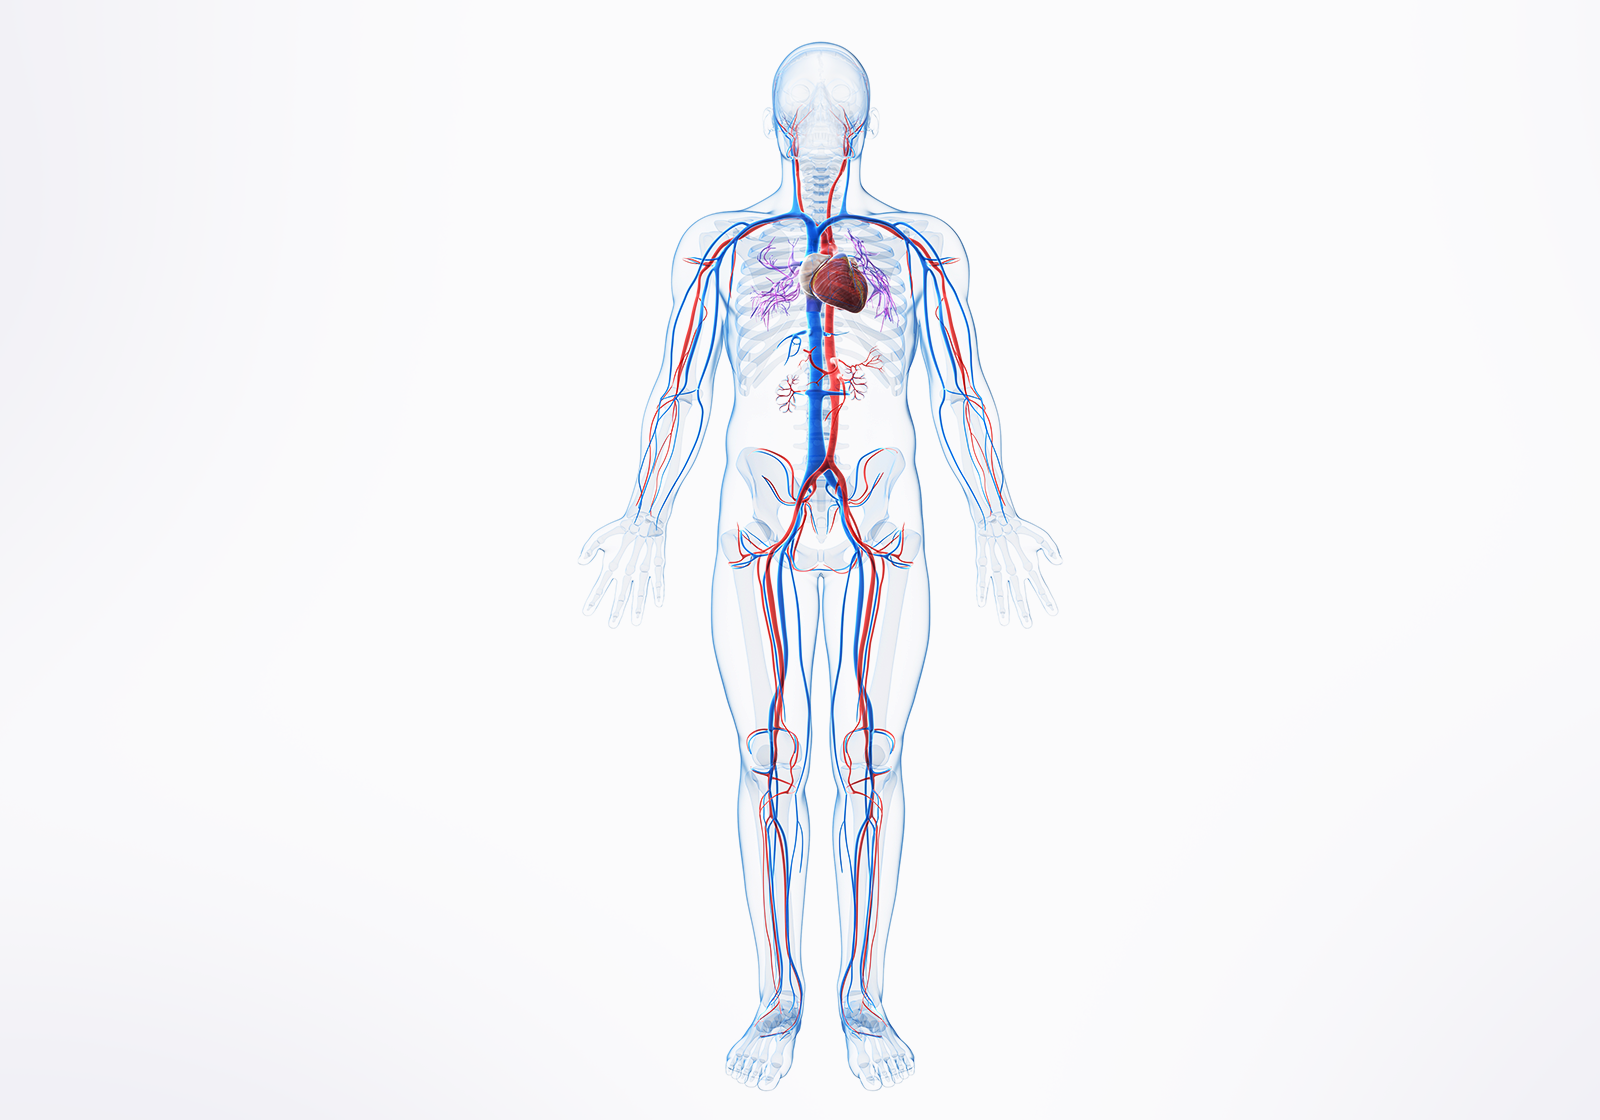

PCI Solution

Lepu Medical leverages cutting-edge technologies and high-performance consumables to deliver comprehensive, full-process vascular intervention solutions. For coronary calcification lesions, Lepu provides a step-by-step device solution portfolio, addressing various types and complexities of calcified lesions, and empowering clinicians with tailored tools for optimal patient outcomes.In the peripheral vascular field, Lepu offers integrated support from diagnosis to treatment, enabling safer, more efficient, and minimally invasive procedures.Through continuous innovation and deep clinical insight, Lepu Medical is committed to advancing vascular reconstruction across both peripheral and coronary domains.

Coronary Calcification Lesion Treatment Solution

Lepu Medical is deeply engaged in the field of cardiovascular intervention, providing comprehensive and step-by-step device solutions for different types of coronary calcification lesions.

Peripheral Solutions

With innovative technologies and high-end consumables as the core, Lepu Medical provide full-process support from diagnosis to treatment, helping clinicians achieve safer, more efficient and more minimally invasive peripheral vascular reconstruction.